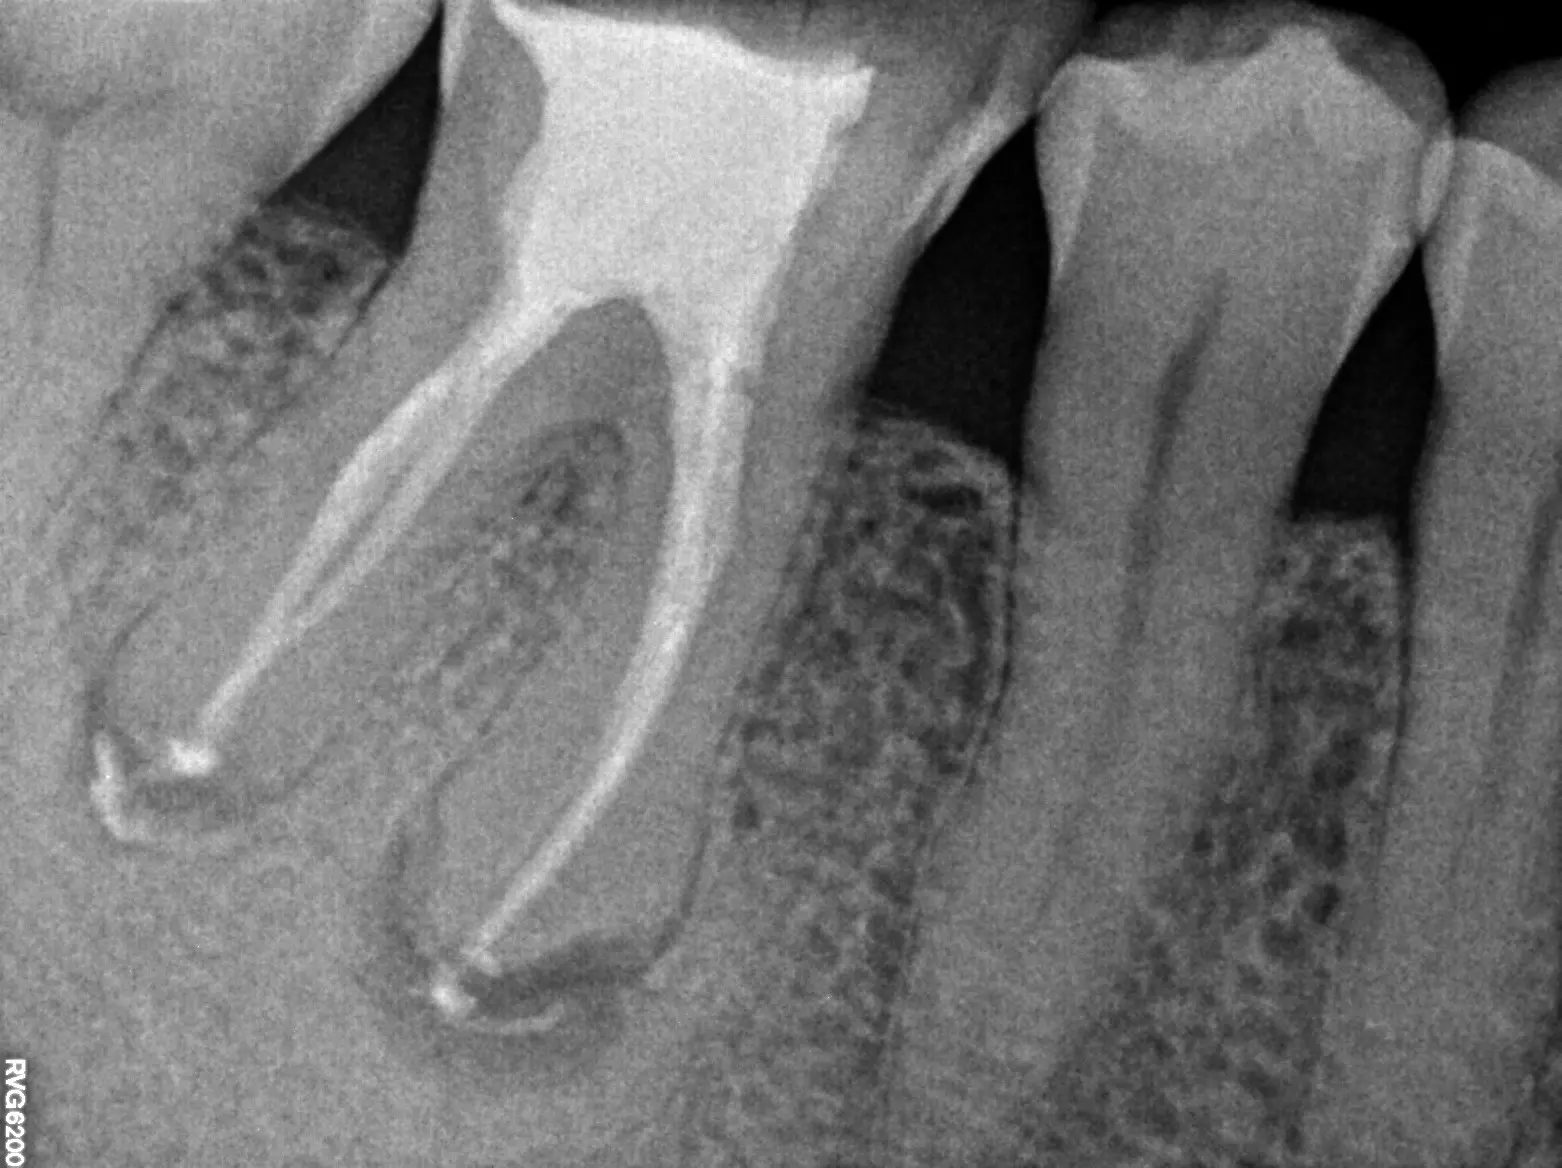

Retreatment involves the doctor reopening the tooth to gain access to the root canal filling material. The restorative material will be removed. The doctors will clean your canals and examine the problematic tooth. Once cleaned, the doctor will fill and seal the canals and place a temporary filling in the tooth.